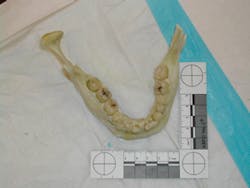

Forensic photography is an element of crime scene investigation that requires the individual to “have a good grasp of photographic terminology and the skills for operating basic camera equipment.”5 Both still and digital photography are accepted methods; however, according to C. Michael Bowers, “Good photographic results are a minimum standard for every competent law enforcement agency. Poor crime scene photography will impact the quality and outcome of every forensic case and reflect negatively on everyone involved.”6 Given these specific parameters, the dental hygienist interested in this aspect of forensics should seek enrollment in photography courses and perhaps turn a popular hobby into a specialty that can be used to help identify the deceased or the perpetrator of a crime. Samples of forensic photography are shown in Figures 2 and 3.